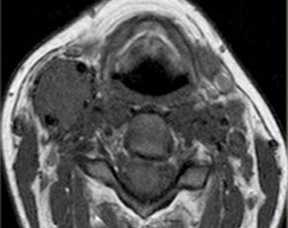

МРТ мягких тканей шеи. Т1-зависимая МРТ в аксиальной плоскости. Каротидная параганглиома справа.

Параганглиомы могут иметь несколько типичных локализаций (тимпаническая, вагусная, феохромоцитома и т.д.) в теле. На шее располагается каротидная параганглиома. Она представляет собой скопление хромафинных клеток в бифуркации общей сонной артерии, между наружной и внутренней. Некоторые из них активны, вырабатывают гормоны, повышающие артериальное давление. Часть опухолей имеет наследственное происхождение. Встречаются двухсторонние параганглиомы. Отличать от других опухолей помогает типичное место расположения, хорошее контрастирование при КТ и МРТ.